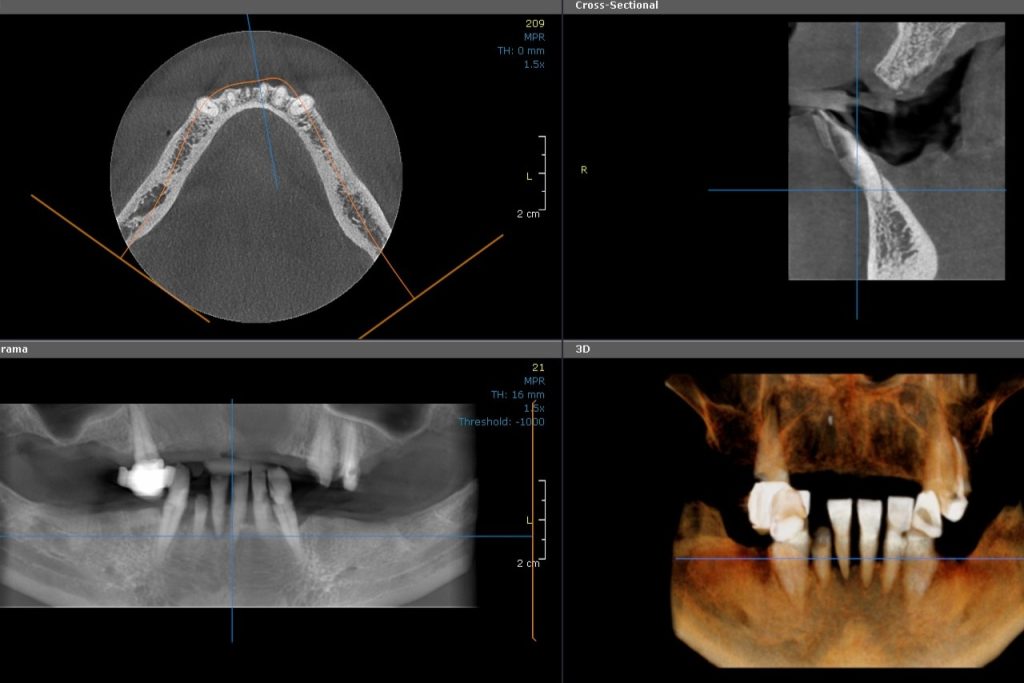

CBCT Maxilla

3D Cone Beam Computer Tomography is used for diagnostics and treatment planning